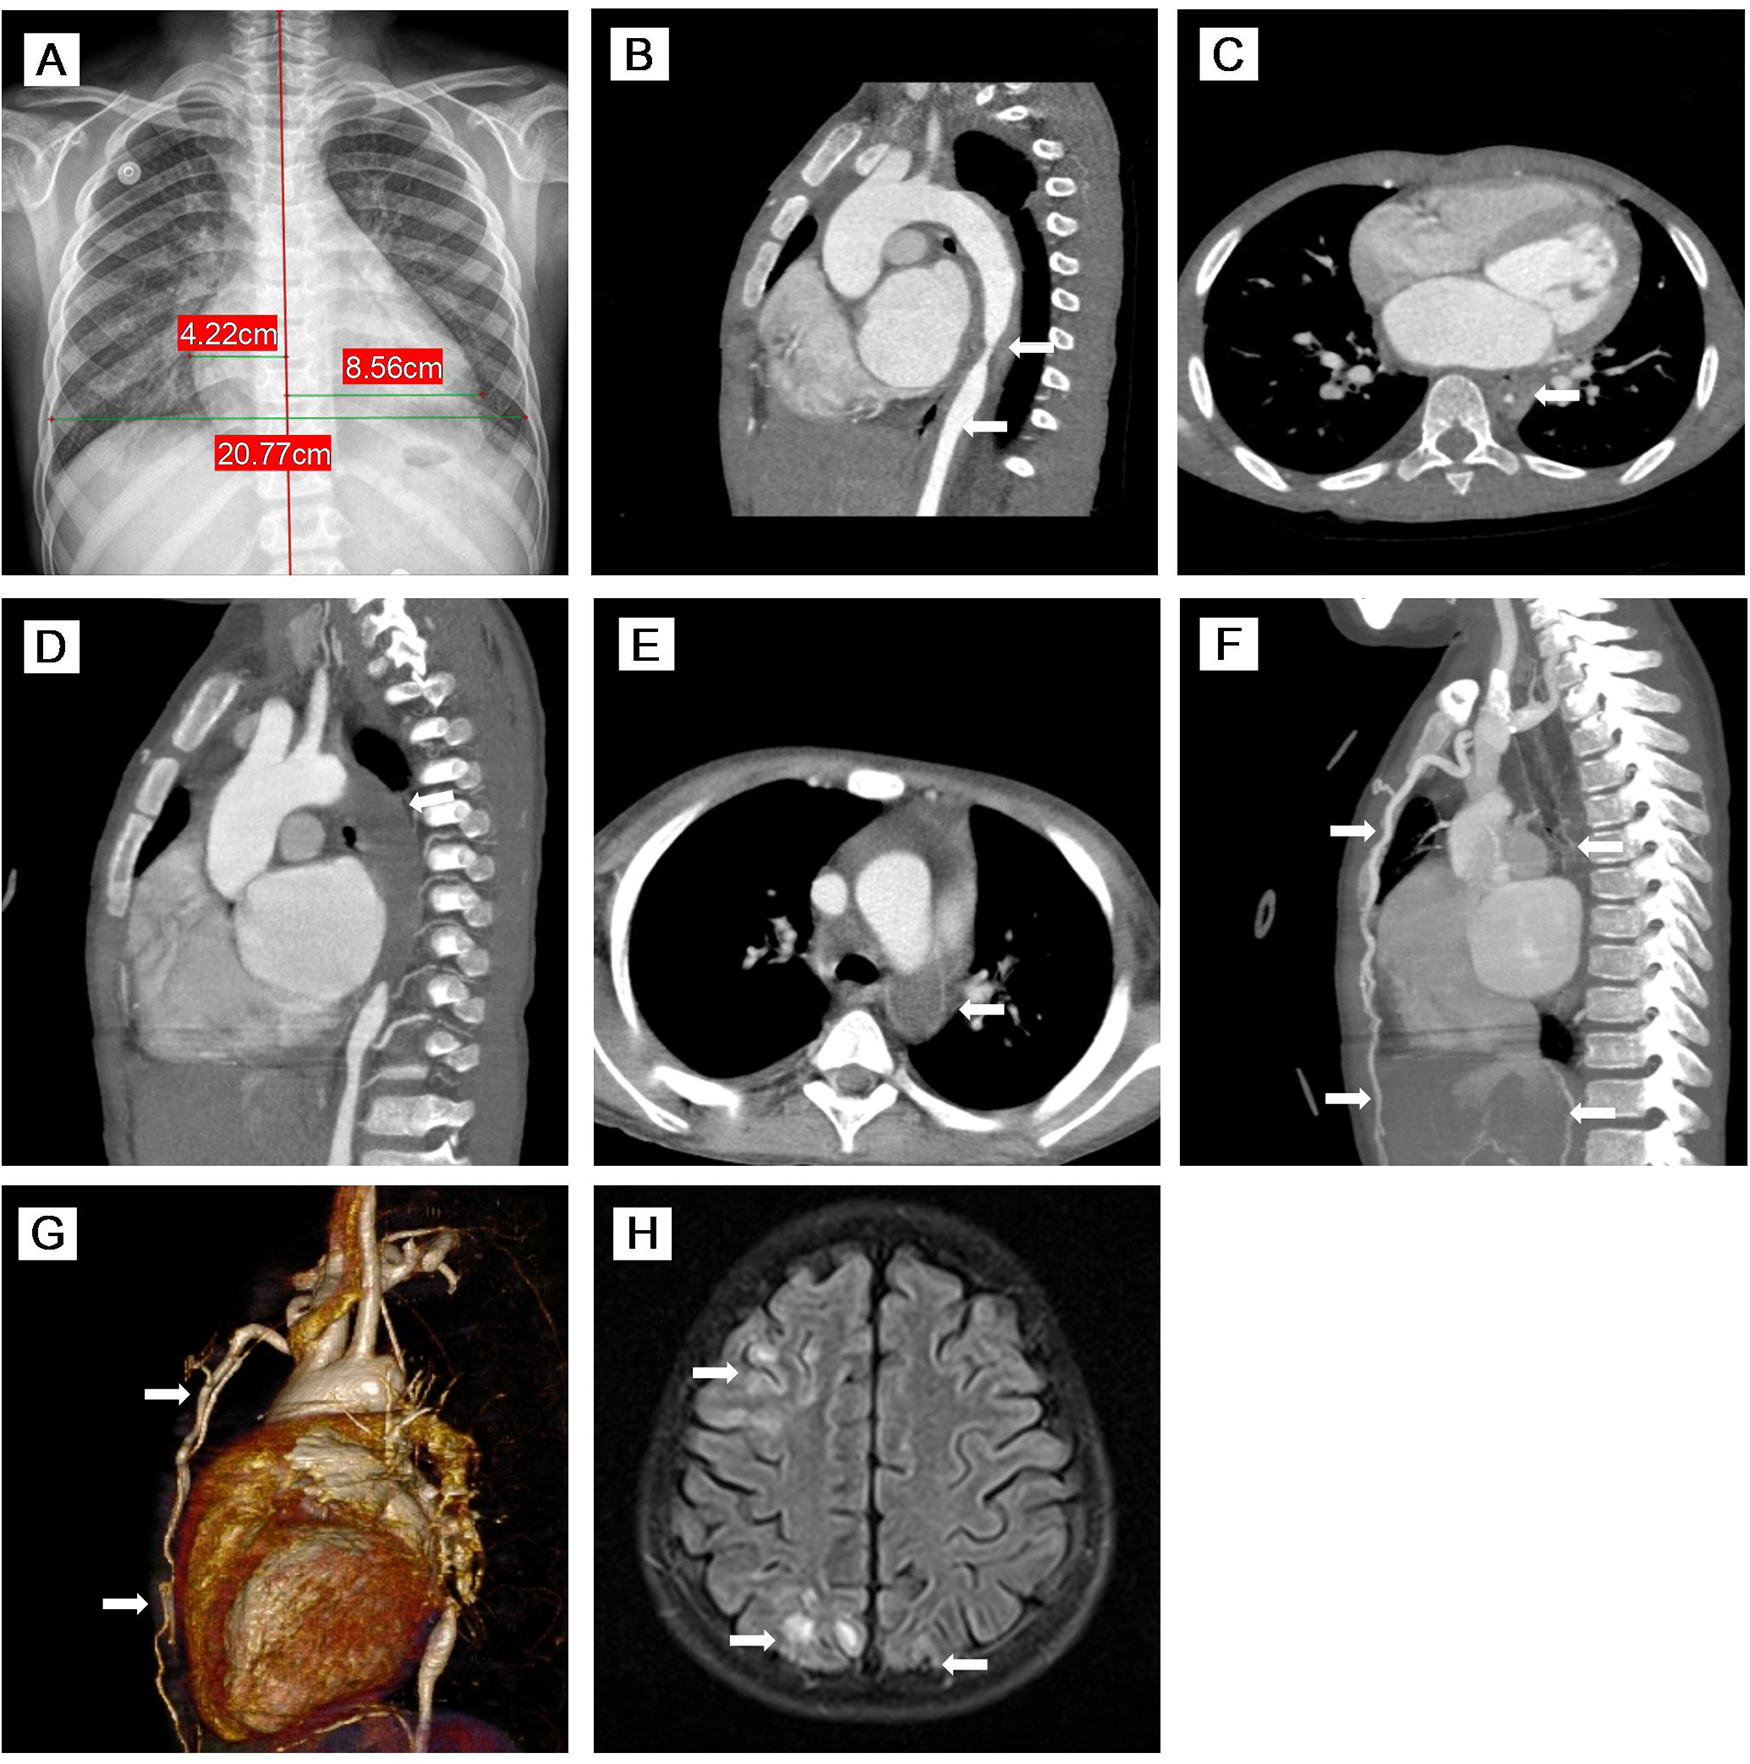

Physical examination on admission showed the following: heart rate 120/min, respiratory rate 26/min, and blood pressure (BP) 159/103 mmHg in his right arm, 124/93 mmHg in his left arm, 87/55 mmHg in his right leg, and 121/106 mmHg in the left leg. Distended jugular veins and weak left radial artery pulsation were found. Class IV systolic murmur in the precordial region was heard. There was no enlargement of liver and spleen. Laboratory evaluations revealed increased N-terminal pro-brain natriuretic peptide (NT-proBNP: 19052 pg/mL), CRP (8.45 mg/L), ESR (32 mm/h), serum creatinine (86 μmol/L), and urea (15.68 mmol/L) with decreased blood potassium (2.9 mmol/L), sodium (128 mmo1/L), and hemoglobin (84 g/L). The purified protein derivative (PPD) skin test and interferon-gamma release assay (IGRA) result were strongly positive. However, all microbiological analyses including TB culture and pathogenic microorganism sequencing were negative. Serum immunoglobulin and complements (C3 and C4) were normal. Antinuclear antibody (ANA) and antineutrophil cytoplasmic antibody (ANCA) were negative. Echocardiography revealed reduced left ventricular ejection fraction (LVEF: 40%) with left heart dilatation, PH (75 mmHg), and moderate mitral insufficiency. Chest x-ray showed significant cardiomegaly (Figure 1A). Chest CT showed calcified left hilar lymph nodes, enlarged mediastinal lymph nodes, patchy and slightly high-density shadows in both lungs, and a small amount of bilateral pleural effusion. CT angiography (CTA) showed occlusion of the proximal left subclavian artery and stenosis of the lumen of the descending and upper abdominal aorta with extensive thickening of the vascular wall (Figures 1B,C). Whole exome sequencing did not indicate any abnormal mutations. Based on the radiological findings and laboratory examinations, he was diagnosed as TB-associated TA (11) complicated with AHF and PH.

Figure 1. (A) Chest x-ray showed significant cardiomegaly. (B–E) MPR images of thoracic CTA. (B) Sagittal view of CTA demonstrated stenosis of the descending aorta and upper abdominal aorta with thickening of the vascular wall. (C) Axial view of CTA showed that the descending aorta was stenosed to 3.1 mm. (D,E) Sagittal oblique view and axial view of CTA indicated complete occlusion of the descending aorta with large thrombus (76 mm in length). (F,G) MIP image and VR reconstruction of CTA revealed complete occlusion of the descending aorta with large thrombus (76 mm in length) and extensive collateral circulation (twisted and dilated right intrathoracic artery, numerous open collateral vessels in the neck and upper mediastinum). (H) Axial view of brain MR imaging revealed high signals on T2 FLAIR images of cortical and subcortical areas of both the occipital lobes and right frontal-parietal lobe. MPR, multiplanar reconstruction; CTA, computed tomography angiography; MIP, maximum intensity projection; VR, volume rendered; MR, magnetic resonance; FLAIR, fluid-attenuation inversion recovery.

The child was re-admitted on day 66 due to worsening HF with lower LVEF (30%), higher PH (70 mmHg), and normal CRP and ESR. During this admission, his BP fluctuated from 175/105–123/74 mmHg, and hemoptysis recurred. Repeated CTA on day 77 and day 92 showed complete occlusion of the descending aorta with large thrombus (76 mm in length) (Figures 1D,E) and extensive collateral circulation (twisted and dilated right intrathoracic artery, numerous open collateral vessels in the neck and upper mediastinum) (Figures 1F,G). In addition to the same medications as the first admission, subcutaneous low-molecular-weight heparin was started on day 78. IVMP therapy (10 mg/kg/day) was administered again on days 93–95.

The patient developed seizure and loss of consciousness while afebrile on day 99. Seizure was controlled with intravenous diazepam. Cranial magnetic resonance angiography (MRA) showed narrowed lumen of the anterior, middle, and posterior cerebral arteries. Brain MR imaging revealed strong signals on T2 fluid-attenuation inversion recovery (FLAIR) images of the cortical and subcortical areas of both the occipital lobes and right frontal-parietal lobe (Figure 1H). After failing to respond to another two doses of TCZ, intravenous infliximab was given for two doses on day 98 and day 112, and IVMP therapy (10 mg/kg/day) again on days 114–116. However, there were still no signs of improvement, and his renal function worsened. Given the complete occlusion of the aorta with large thrombus and aggravating life-threatening HF without response to any medication, balloon angioplasty was performed and catheter-directed thrombolysis with urokinase and heparin was started on day 127. Four days after surgery, the patient worsened suddenly with increased shortness of breath, decreased heart rate, and dropping of oxygen saturation to 60%. The patient died on day 133 (Figure 2).